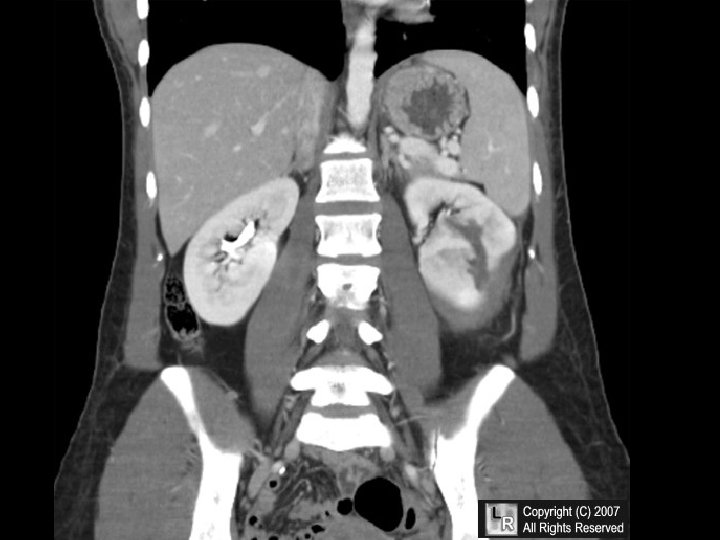

INFARCTION • Defined as an area of necrosis* secondary to decreased blood flow • HEMORRHAGIC vs. ANEMIC • RED vs. WHITE – END ARTERIES vs. NO END ARTERIES • ACUTE ORGANIZATION FIBROSIS

INFARCTION FACTORS • NATURE of VASCULAR SUPPLY • RATE of DEVELOPMENT – SLOW (BETTER) – FAST (WORSE) • VULNERABILITY to HYPOXIA – MYOCYTE vs. FIBROBLAST • CHF vs. NO CHF